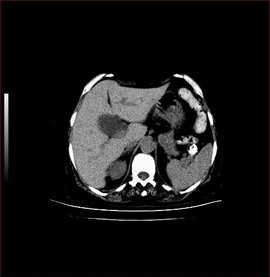

B超发现胆囊壁毛糙、胆囊壁增厚怎么办(图示)

600x450 - 81KB - JPEG